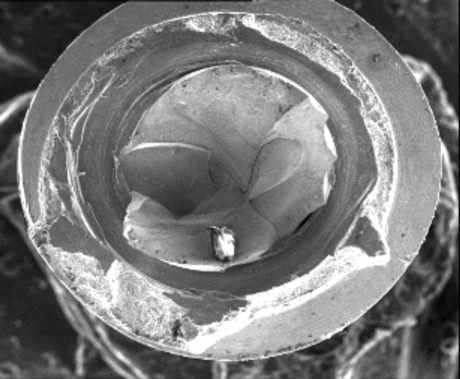

When subjected to loading, cyclic or static, metals may undergo "creep." Creep is a type of metal deformation that occurs at stresses below the yield strength of a metal.22 Regarding dental implants, this may lead to alteration of the platform of the implant through distortion of the connection or by the coronal aspect at the platform becoming "out of round." With an internal type of connection, under continued loading, this may eventually lead to loosening of the abutment on the implant as the intimacy of the fit between the parts decreases or even a fracture of the implant coronally. An external hex connection undergoing creep will demonstrate rounding of the points of the hex. The potential for creep is determined by measuring the percentage of elongation of a material. A higher percentage of elongation indicates a softer metal and higher possible degree of creep. CP-Ti demonstrates a decreasing percentage of elongation from grade 1 to 4 due to a decrease in the softness of the metal. Furthermore, comparisons of CP-Ti grade 4 with Ti-6Al-4V grade 5 reveal a significantly lower potential for creep associated with the alloy.20,23

As discussed, yield strength defines the stress at which metal begins to plastically deform. When presented with off-axis loads over time, an external hex connection on an implant may undergo creep, which leads to rounding of the points because this is where the stress is concentrated. As the points on the external hex deform, they permit greater micromovement of the abutment, which leads to greater stress being placed on the abutment screw and can result in fracture of the screw (Figure 9). When an implant is fabricated from CP-Ti, even grade 4, there is a greater potential for this problem than if it is fabricated from titanium alloy grade 5; however, it occurs less frequently in wider diameter implants.

(9.) Deformation of the external hex connection and subsequent fracture of the coronal aspect of a CP-Ti grade 4 implant leading to fracture of the abutment screw at the interface.

Figure 9